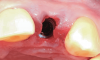

Fig 15. The provisional crown removed to demonstrate the ideal appearance of the soft-tissue contour prior to permanent crown insertion.

Figure 15